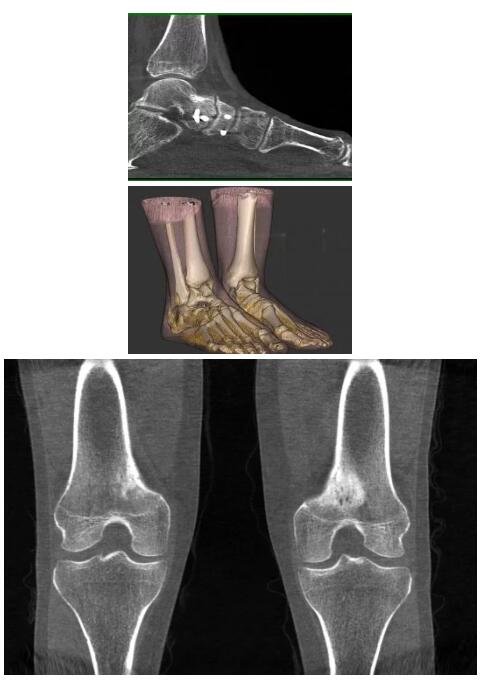

以下是這些“特立獨行”的CT所拍出來的圖像: